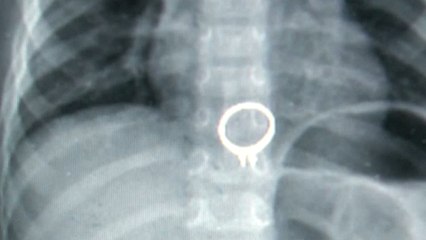

A Florida woman mistakenly swallows a $5,000 diamond at a charity event. Thankfully she had a colonoscopy scheduled for the next day. Problem solved.